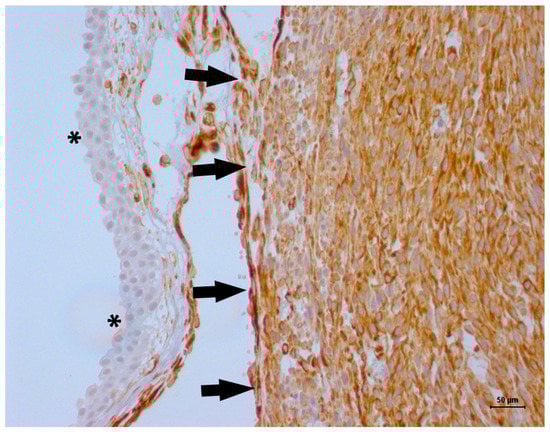

2. Case Description